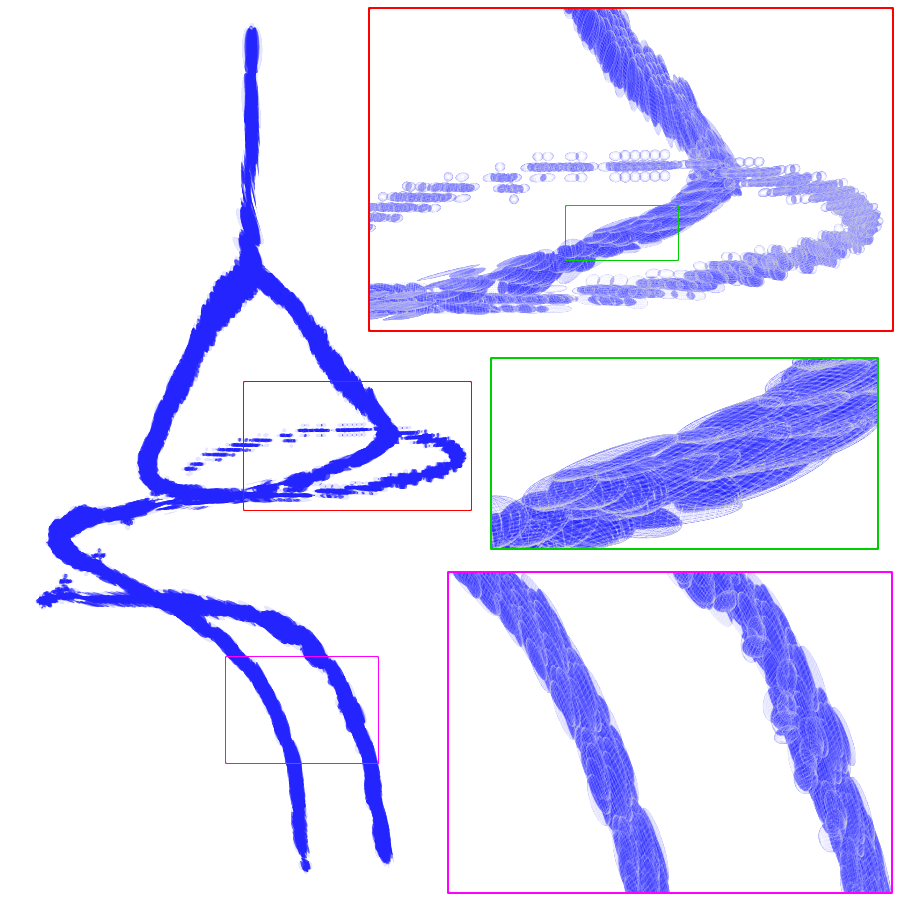

Geodesic paths are determined by back-tracing when different regions collide. The connecting geodesic is extracted minimizing at the collision grid-points. The aFM maps, i.e. ; the Voronoi index map , representing the label associated to each propagating seed; and the Tag , representing the state of each grid-point (Front, Visited, Far), are then updated within the collided regions, so that these merge as one and the front is consistent with the unified resulting region. This is continued until all regions merge.

Initialization. The seeds are aligned towards the vessels’ mid-line with a constrained gradient descent, resulting in an initial set of sources . All 26-connected components initialize the aFM maps, i.e., , , , and constitute also the initial geodesics .

Fast Marching Step. The aFM maps are updated by following an informative propagation scheme. We refer to [4] for the 3D aFM step considering the 48 simplexes in the 26-neighbourhood of the Front grid-point with minimal .

Path Extraction. Collision is detected when Visited grid-points of different regions are adjacent. A connecting is determined by linking the back-traced minimal paths from the collision grid-points to their respective sources with a gradient descent on (fig. 2). The associated integral geodesic length is computed and the connectivity in is updated in the form of an adjacency list. Lastly, the grid-points of the extracted are further considered as path seeds in the updating scheme, since furcations can occur at any level of the connecting minimal paths.

Fast Updating Scheme. A nested aFM is run only in the union of the collided regions using a temporary independent layer of aFM maps, where , , and . Ideally, the nested aFM is run until complete domain exploration, however, to speed up the process, the propagation domain is divided into the solved and unsolved sub-regions, and the update is focused on the latter (fig. 2). The boundary geodesic values of equal the geodesic distances at the collision grid-points. Lastly, the aFM maps are updated as: , , and .

3.2 Connected Geodesic Paths as Vascular Tree

Representative examples of degraded synthetic images from SVT and the respective GT are shown in fig. 4 together with the connected graphs extracted by VTrails. Analogously, the same set of images are reported for the real images TOF and CTA in fig. 4. Qualitatively, the extracted set of connected geodesic paths shows remarkable matching with the provided GT in all cases. First, we verify the acyclic nature of the graph. We found no cycles, degenerate graphs and unconnected nodes, meaning that the extracted connected geodesic paths represent a connected geodesic tree. Precision and recall are then evaluated for the identified branches. Also, error distances are determined as the connected tree’s binary distance map evaluated at GT. Average errors () precision and recall are reported (meanSD) in table 1. Note that no pruning of any spurious branches is performed in the analysis.

We presented VTrails, a novel connectivity-oriented method for vascular image analysis. The proposed method has the advantage of introducing the SLoGS filterbank, which simultaneously synthesizes a connected vesselness map and the associated tensor field in the same mathematically coherent framework. Interestingly, recent works [17, 9] are exploring Riemannian manifolds of tensors for high-order vascular metrics, however the coherent definition of a tensor field is not trivial for an arbitrary scalar image, as its topology cannot be generally approximated simply by an ellipsoid model [14]. The steerability property of SLoGS stands out as key feature for i. reducing the dimensionality of the kernels parameters in 3D, ii. determining the filterbank’s rotation-invariance and iii. optimizing the 3D filtering complexity in the OLA. Also, the combined rotation- and curvature-invariance of the filtering process results in branch-points that coincide with the locally integrated center of mass of the multiple SLoGS filter responses. This explains the strong response in the CVM at the branch-point in fig. 3. Regarding the acyclic connectivity paradigm employed in VTrails, we experimentally verified that the resulting set of connected geodesic paths forms a tree. The assumption of a vascular tree provides a natural and anatomically valid constraint for 3D vascular images, with few rare exceptions, such as the complete circle of Willis [5]. It is important to note that the proposed algorithm can include extra anatomical constraints to correct for locations where the vascular topology is not acyclic or where noise it too high. Note that despite the optimal formulation of the anisotropic front propagation, a limitation of the greedy acyclic connectivity paradigm is the possibility of miss-connecting branches, potentially disrupting the topology of the vascular network. Overall, promising results have been reported from this early validation, with a fully-automatic extraction configuration. Missing branches occur in correspondence of small vessels, where the effect of degradation is predominant: tiny terminal vessels completely occluded by the corrupting shadows will not automatically produce seeds, hence cannot be recovered under such configuration. Globally, values are comparable to the evaluation tolerance , suggesting that the connected geodesic paths extracted by VTrails lie in the close neighbourhood of the vessels’ centerlines. Moreover, the reported values are comparable regardless the level of degradation. Future developments will address the optimization of the CVM integration strategy in section 2.1 to account for an equalized response over the vascular spatial frequency-bands. Also, the topological analysis of vascular networks on a population of subjects will be investigated in future works to better embed priors in the acyclic connectivity paradigm.